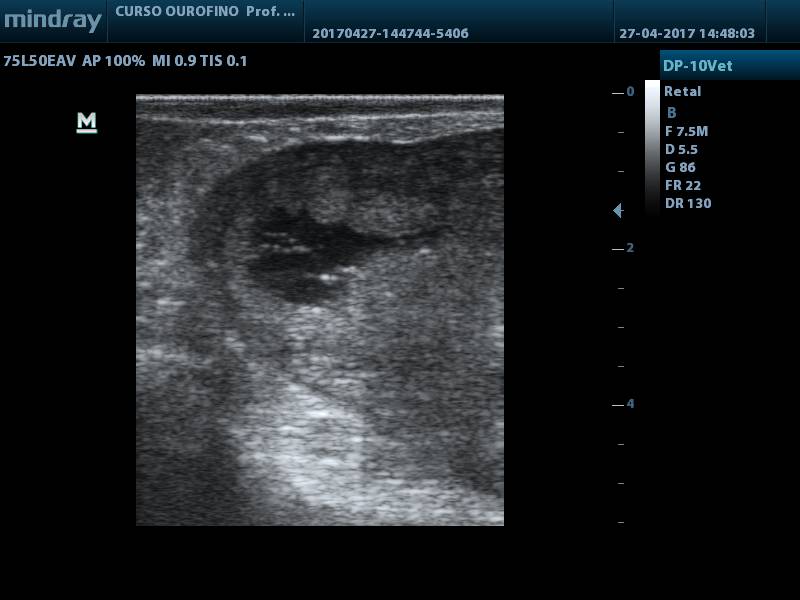

Após a lavagem, foi realizado um novo exame ultrassonográfico, o qual mostrou acentuada diminuição do conteúdo no lúmen uterino, com pequena quantidade de pontos hiperecóicos (fig. 6). Um novo exame ultrassonográfico foi realizado 14 dias (D+ 50) após o último lavado e pode-se constatar a ausência de líquido no interior dos cornos uterinos (fig. 7), concluindo que o animal não apresentava mais alterações.

Figura 7.